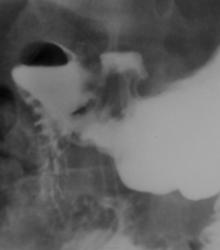

Очень показательно. Мне чудится-видится или все таки этот кратер с признаками пенетрации?

И то, и другое. Но первоначально, думаю, была язва, которая малигнизировалась-выходит за контуры желудка, конвергенция итд. Над кратером определяется пузырек воздуха, поэтому возник вопрос о пенетрации. Если делали ФГДС-что на биопсии?

Пенетрирующая язва. Малигнизация возможна.

Интересный случай! Представленные снимки: картина изъязвления антрального отдела желудка по малой кривизне, с пенетрацией. Согласен с автором демонстрации- на представленных снимках нет убедительных признаков рака желудка ( хотя разбирая методику исследования, следует сказать,что оптимально бы посмотреть желудок лёжа, в условиях двойного контрастирования, в этом случае, возможно выявились бы признаки инфильтрации малой кривизны желудка) . Считаю, что определяющим в постановке диагноза должны быть результаты гистологии: что это- рак желудка с изъязвлением или язвеннная болезнь с пенетрацией.Принципиально разные по тактике ведения состояния. Показны УЗИ оргнов брюшной полости и РКТ.

При пальпации за экраном и дозированной компрессии тубусом локальная болезненность только в проекции "дна" ниши.

куда предположительно пенетрация? сальник? поджелудочная? свободного газа не наблюдалось в брюшке?

Нет, свободного газа не было, не было и клиники перфорации.

Интересно мнение УЗИ, по ПЖЖ. Есть конвергенция складок желудка к данному образованию, образование выходит за пределы контура желудка. Не определятся дополнительных характерных признаков дополнительного образования желудка на данном уровне визуализации.

Закл. Признаки доброкачественного воспалительного изменения антральной части желудка. Не исключается каллезная язва, каллезная язва с осложнениями. Не искл. пенертирующее воздествие на тело ПЖЖ.